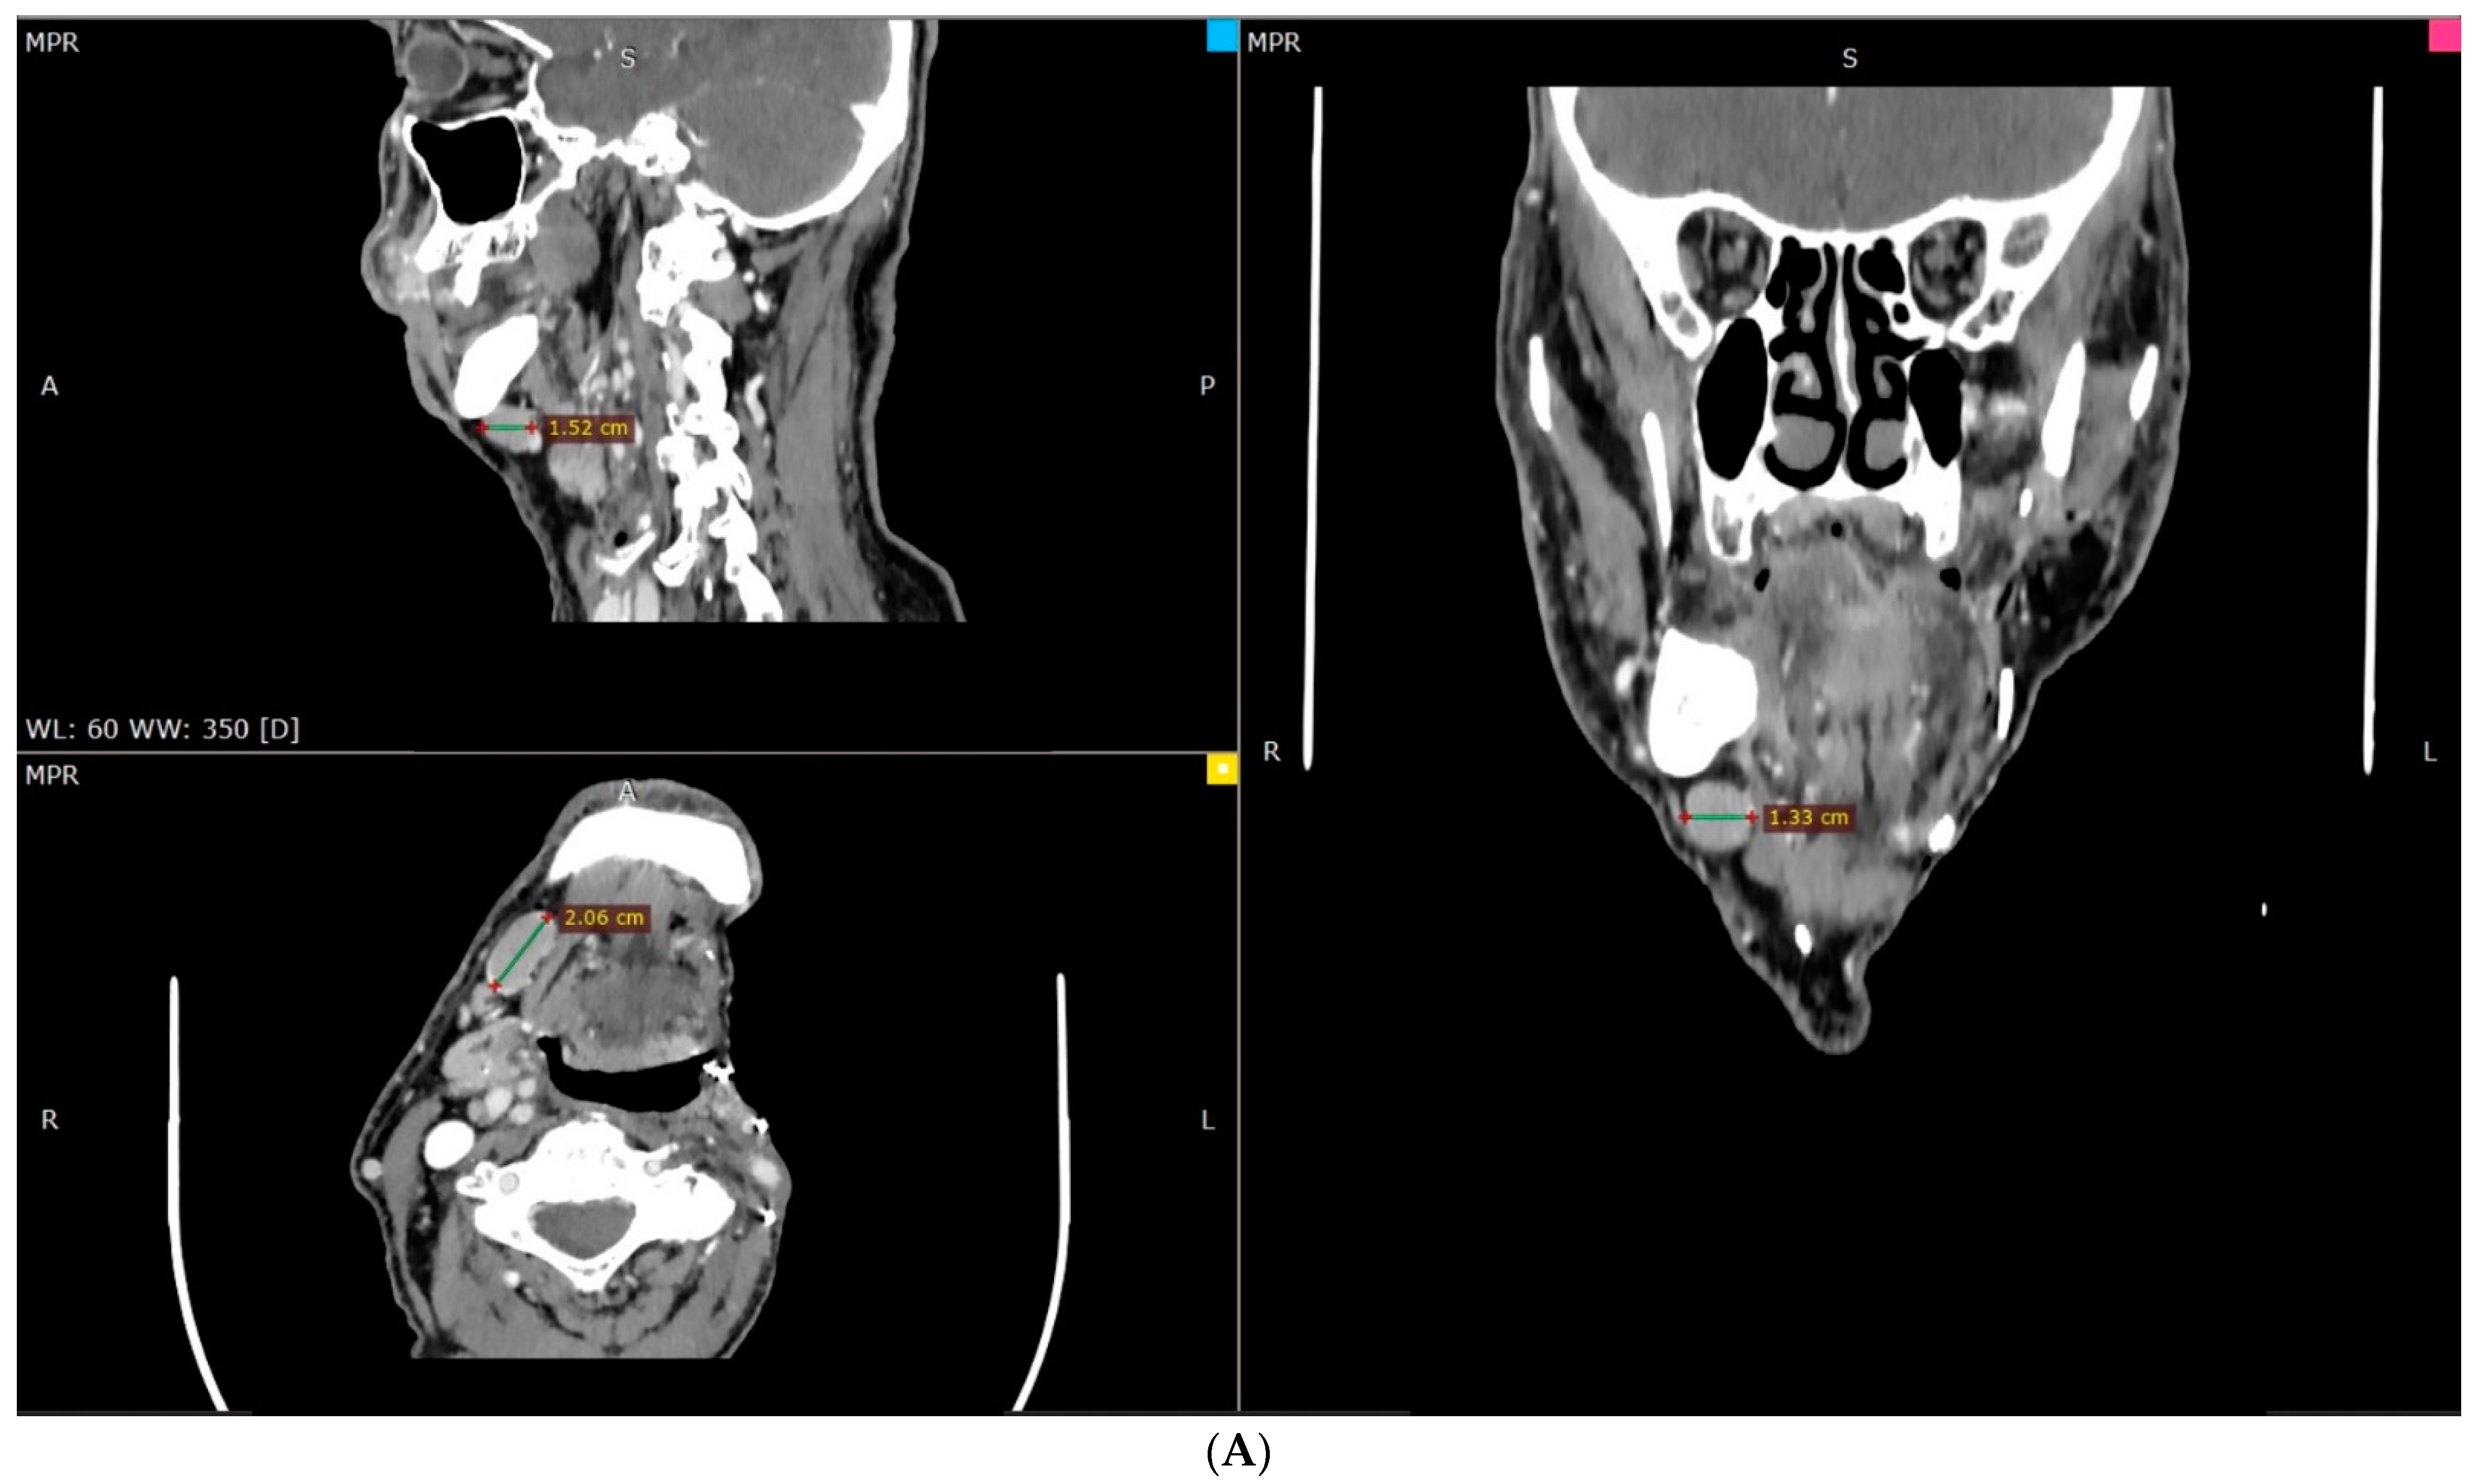

2. Case Description